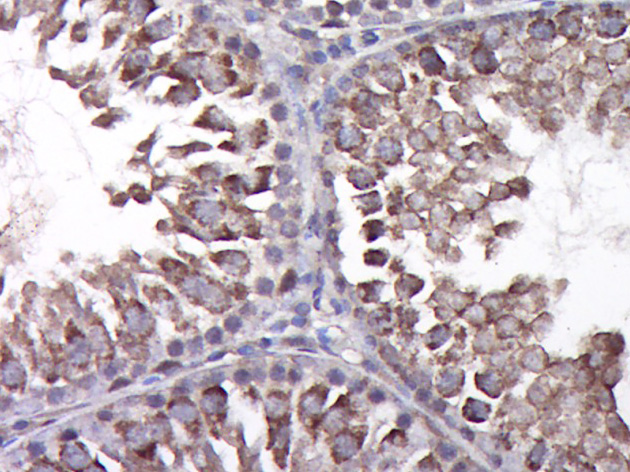

Paraformaldehyde-fixed, paraffin embedded (Rat testis); Antigen retrieval by boiling in sodium citrate buffer (pH6.0) for 15min; Block endogenous peroxidase by 3% hydrogen peroxide for 20 minutes; Blocking buffer (normal goat serum) at 37°C for 30min; Antibody incubation with (CCL4) Polyclonal Antibody, Unconjugated (bs-1046R) at 1:400 overnight at 4°C, followed by operating according to SP Kit(Rabbit) (sp-0023) instructions and DAB staining.